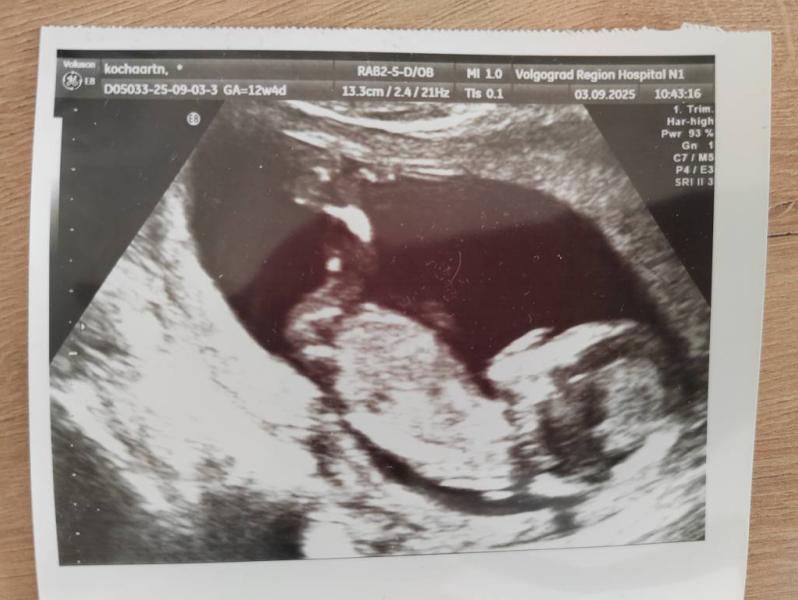

Мальчишка.... После 2 девочек слышать на УЗИ "у вас мальчик" - максимально необычно. Все радуются, поздравляют и говорят, что это счастье. А я хотела девочку. Потому что с ними мне понятно, знакомо. С мальчиками же появляется куча вопросов : вдруг я не смогу его любить также как девчонок? Вдруг я его разбалую, не смогу воспитать "мужчину", а вдруг наоборот, в стремлении воспитать сильного, выносливого - не додам любви и мой сын будет страдать от отсутствия поддержки? Я не знаю, как буду реагировать, когда он приведёт девочку, когда у него начнётся половая жизнь, когда придёт время армии? Как это пережить?

Мне на вашем сроке тоже говорили мальчик , родила девочку 🫣

На сроке 17 недель уже отчётливо мальчик и девочка отличаются, там не угол наклона полового бугорка уже смотрят) грамотный узист не спутает точно